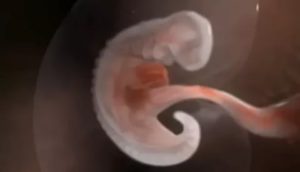

Срок беременности все еще довольно мал. Но плодное яйцо продолжает развиваться независимо от того, известно ли об этом будущей маме.

На 4 неделе оно превращается в эмбрион, у которого уже образуются зачатки всех трех зародышевых листков.

Каждый из них отвечает за развитие определенных систем органов: внешний – за кожу и нервную систему, средний – за костно-мышечную и сердечно-сосудистую системы, а внутренний – за развитие легочной и пищеварительной систем.